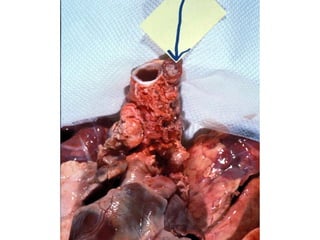

Preparation for a  tracheotomy , which is the  surgery  to open this airway in the trachea.

Tracheotomy  procedure to open an airway in the trachea

A  tracheostomy  is the  hole  made in the trachea following a tracheotomy

Tracheostomy

Note scar from tracheotomy done in childhood